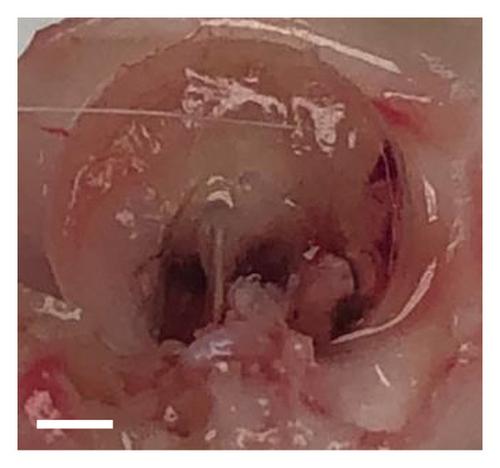

Chronic tympanic membrane (TM) perforation increases patient susceptibility to infection, hearing loss, and other side effects. Current clinical treatment, surgical grafting, can result in detrimental side effects including nerve damage, dizziness, or hearing loss. Therefore, it is essential to develop novel therapeutic procedures that can induce or accelerate healing in minimally or noninvasive approaches. Cell-free therapies have safety advantages over stem cells and are logistically favorable for clinical use. The regenerative potential by mesenchymal stem cell-conditioned media (CM) has been promising. In this study, poly(lactic-co-glycolic acid) (PLGA) microspheres with CM encapsulated have been developed as a cell-free alternative regenerative treatment for TM perforation. The results suggest that the PLGA microspheres were capable of encapsulating and releasing CM for up to 21 days. The in vitro scratch wound proliferation assays showed increased wound healing ability of CM-loaded microspheres. In vivo guinea pig models treated with CM drops and CM-loaded microspheres using a thermoresponsive gel carrier demonstrated potential for wound healing in TM perforation. These studies provide a basis for further examination of the delivery of stem cell CM and investigation of time-dependent wound healing, long-term ototoxicity, and hearing restoration.